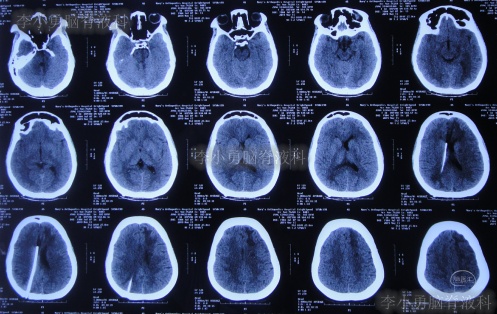

患者2019年2月初,因数次出现发作性黑蒙,2019年2月10日就诊于当地的河南省永城市某医院,查头颅CT未见明显异常(图-1);次日再查头颅核磁、颈椎核磁(图-2、图-3)后发现小脑扁桃体下疝畸形合并脊髓空洞。

图-2:2019年2月12日头颅核磁

图-3:2019年2月13日头颅核磁

小脑扁桃体下疝减压术后20天即2019年3月6日,查头颅、颈椎核磁发现仍有脊髓空洞(图-8、图-9)。

图-8:2019年3月6日头颅核磁

图-9:2019年3月6日头颅核磁